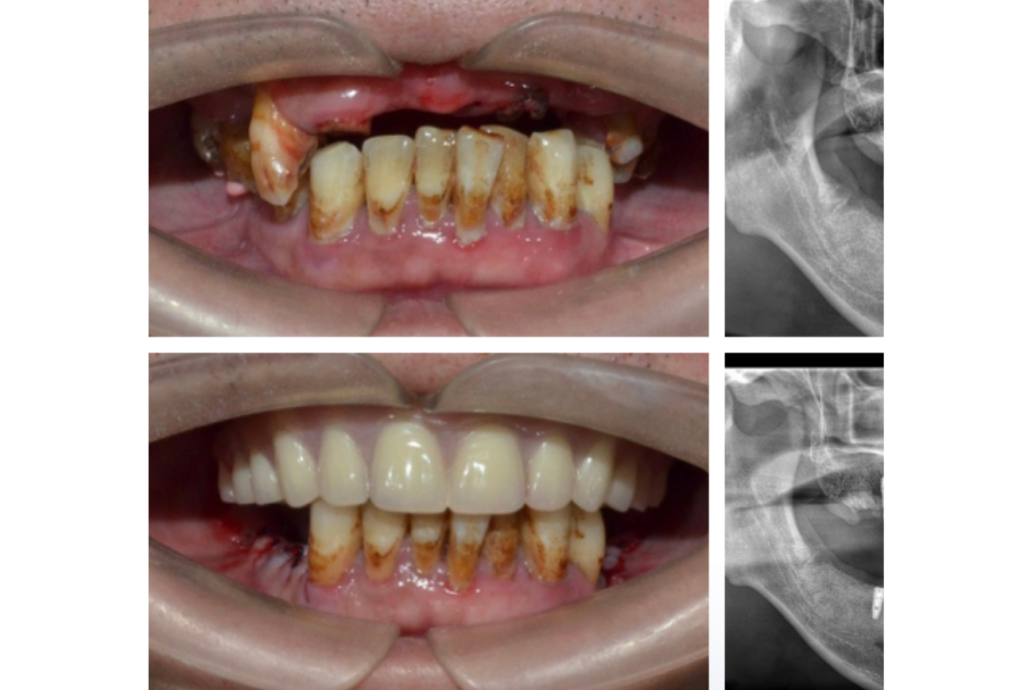

All-on-4 重拾笑容,自信再現 結合四支植體設計,手術當天即可裝上臨時假牙, 快速恢復咀嚼與美觀功能,讓笑容不再等待。 立即預約諮詢 全程專屬規劃 為你打造高效、穩定的全口重建體驗 從評估到笑容重現,每一步都由專業團隊精準掌控。 全口檢查與影像評估 透過3D斷層與影像掃描,完整掌握骨質、神經與顎骨條件,制定安全植牙計畫。 數位重建與手術規劃 電腦模擬骨架與角度,精準製作導引板,提升植體角度與深度的準確性。 植入四支植體 採用前2支直植、後2支傾斜植入方式,減少植骨需求,穩定支撐全口假牙。 安裝臨時固定假牙 手術當天即可裝上臨時假牙,立即恢復基本咀嚼與美觀功能。 骨整合與正式假牙製作 約2–4個月後待植體穩定,製作最終全瓷或混合式固定假牙,兼具美觀與耐用。 定期追蹤與維護 每3–6個月回診檢查植體與牙齦狀況,確保長期穩定與口腔健康。 精準・安全・快速恢復 全口缺牙患者打造的重建方案 從數位影像評估、手術規劃到人工牙冠裝戴,全程由專科醫師親自操作。透過 3D 導引技術與數位導航,降低風險、縮短恢復期,讓全口植牙更安全、穩定又快速。 數位手術規劃: 精準掌握骨質條件,預先模擬植牙位置。 固定式修復: 假牙穩固不晃動,外觀自然舒適。 縮短療程時間: 一次完成植入與修復,減少等待期。 免植骨方案: 避開上顎竇與神經,降低手術風險。 全口重建流程超簡單 三步驟,重拾自然笑容與穩定咬合 1 全口3D影像與數位規劃 透過3D斷層與電腦模擬分析,評估骨質與角度,量身設計全口重建方案。 2 四支植體精準植入 採用前直後斜的四支植體設計,免植骨、傷口小,當天即可完成手術。 3 當日安裝臨時假牙 手術當天裝戴臨時固定假牙,立即恢復外觀與咀嚼,後續再製正式全瓷或混合假牙。 患者見證 他們的笑容,證明一切 All-on-4 不只是恢復牙齒功能,更讓生活重新找回自信。 林先生全口重建患者 ★★★★★ Rated 5 out of 5 「原本以為要分好幾次手術,沒想到當天就能裝上假牙!吃飯、說話都很自然,像換了一副新人生!」 蔡小姐長期配戴活動假牙患者 ★★★★★ Rated 5 out of 5 「以前活動假牙常鬆脫又不舒服,改做 All-on-4 之後完全不同。假牙穩、咬合正常,笑起來也更自然漂亮!」 黃先生全口缺牙患者 ★★★★★ Rated 5 out of 5 「醫師幫我用四支植體完成全口重建,過程輕鬆、恢復快。現在可以正常吃飯、講話也更有自信!」 成功案例 0 + 病患滿意度 0 /5 療程成功率 0 % 開始之前,你一定想知道的事 為什麼越來越多人選擇All-on-4 全口重建?一日完成:手術當天即可植入並裝上臨時假牙。植體數少:僅需四支植體即可支撐整排牙齒。恢復快速:手術後即可進食、恢復日常生活。固定式假牙:穩定舒適,不易晃動。美觀自然:假牙形態貼近真牙,笑容更自信。 Q1. All-on-4 手術會痛嗎? 手術中會施打局部麻醉,術中幾乎無痛感,術後僅有輕微腫脹不適,通常 2–3 天即可恢復日常活動。 Q2. All-on-4 需要多久完成? 多數情況可在手術當天完成植入與臨時假牙裝戴,正式假牙於 2–4 個月後安裝完成。 Q3. 誰適合做 All-on-4? 全口缺牙、活動假牙配戴不穩或骨量不足者最適合,醫師會依骨質與健康狀況進行評估。 Q4. All-on-4 比傳統全口植牙好在哪? 僅需四支植體、手術時間短、免植骨、恢復快,整體費用與療程時間皆更經濟有效率。 Q5. All-on-4 能維持多久? 若維持良好清潔與定期回診,植體可使用十年以上,多數患者能長期穩定無異狀。 想了解更多?立即預約諮詢! 由專業醫師親自評估你的牙齒狀況,為你規劃最合適的方案,展現自然又自信的笑容。 立即預約諮詢